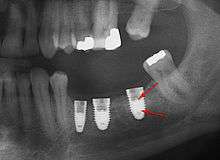

Screw fracture

Fracture of abutment screws (arrow) in 3 implants required removal of the remainder of the screw and replacement.